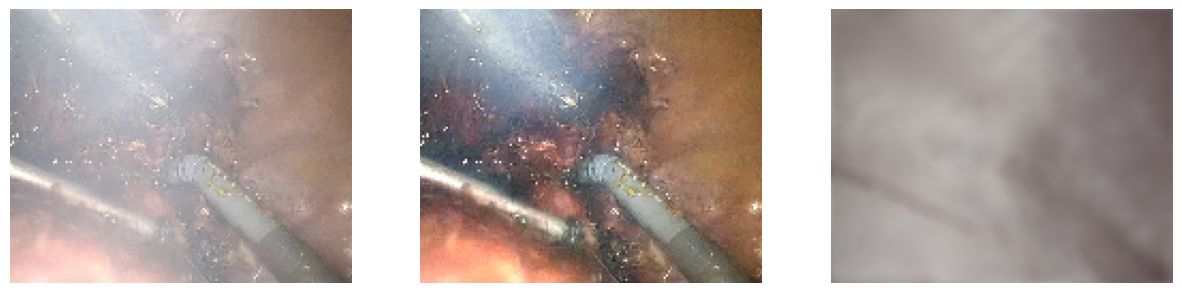

Desmoking Results

Our transformer-based model removes surgical smoke in real time, recovering scene content behind dense smoke with minimal color distortion.

Liver — Ours (Synthetic Only)

Liver — Ours (Fine-tuned)

Qualitative Comparisons

Qualitative comparisons across representative scenes (liver and stomach). Our method recovers scene content behind dense smoke with minimal color distortion and fewer artifacts compared to existing dehazing and desmoking approaches.